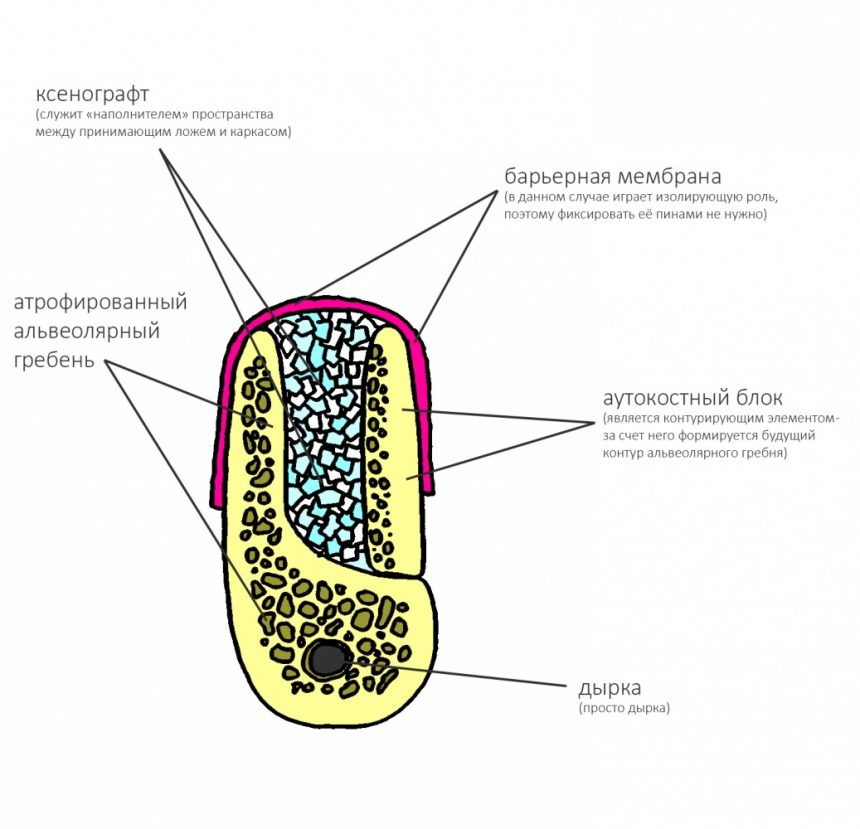

И, наконец, «ламинарная техника»:

и прочие «сендвичи»:

являются примерами комбинированных методик, сочетающих в себе как пересадку крупного костного фрагмента, так и использование резорбируемой каркасной НКР.

Как видите, в данном случае с помощью блока всего лишь задан каркас, а между блоком и принимающим ложем, по сути,ничего нет:

Изоляция этой области с помощью барьерной мембраны:

создает условия для миграции клеток, предотвращая прорастание мягких тканей между аутокостным блоком и принимающим ложем. И, как результат:

фактически, «из ничего» мы формируем достаточный объем костной ткани для установки имплантов.

Барьерная мембрана может играть две роли, изолирующую и контурирующую.

В случае, если контур будущего альвеолярного отростка задается какими-то другими элементами (блоком, пластиной, сеткой и т. д.), в фиксации большинства мембран нет необходимости